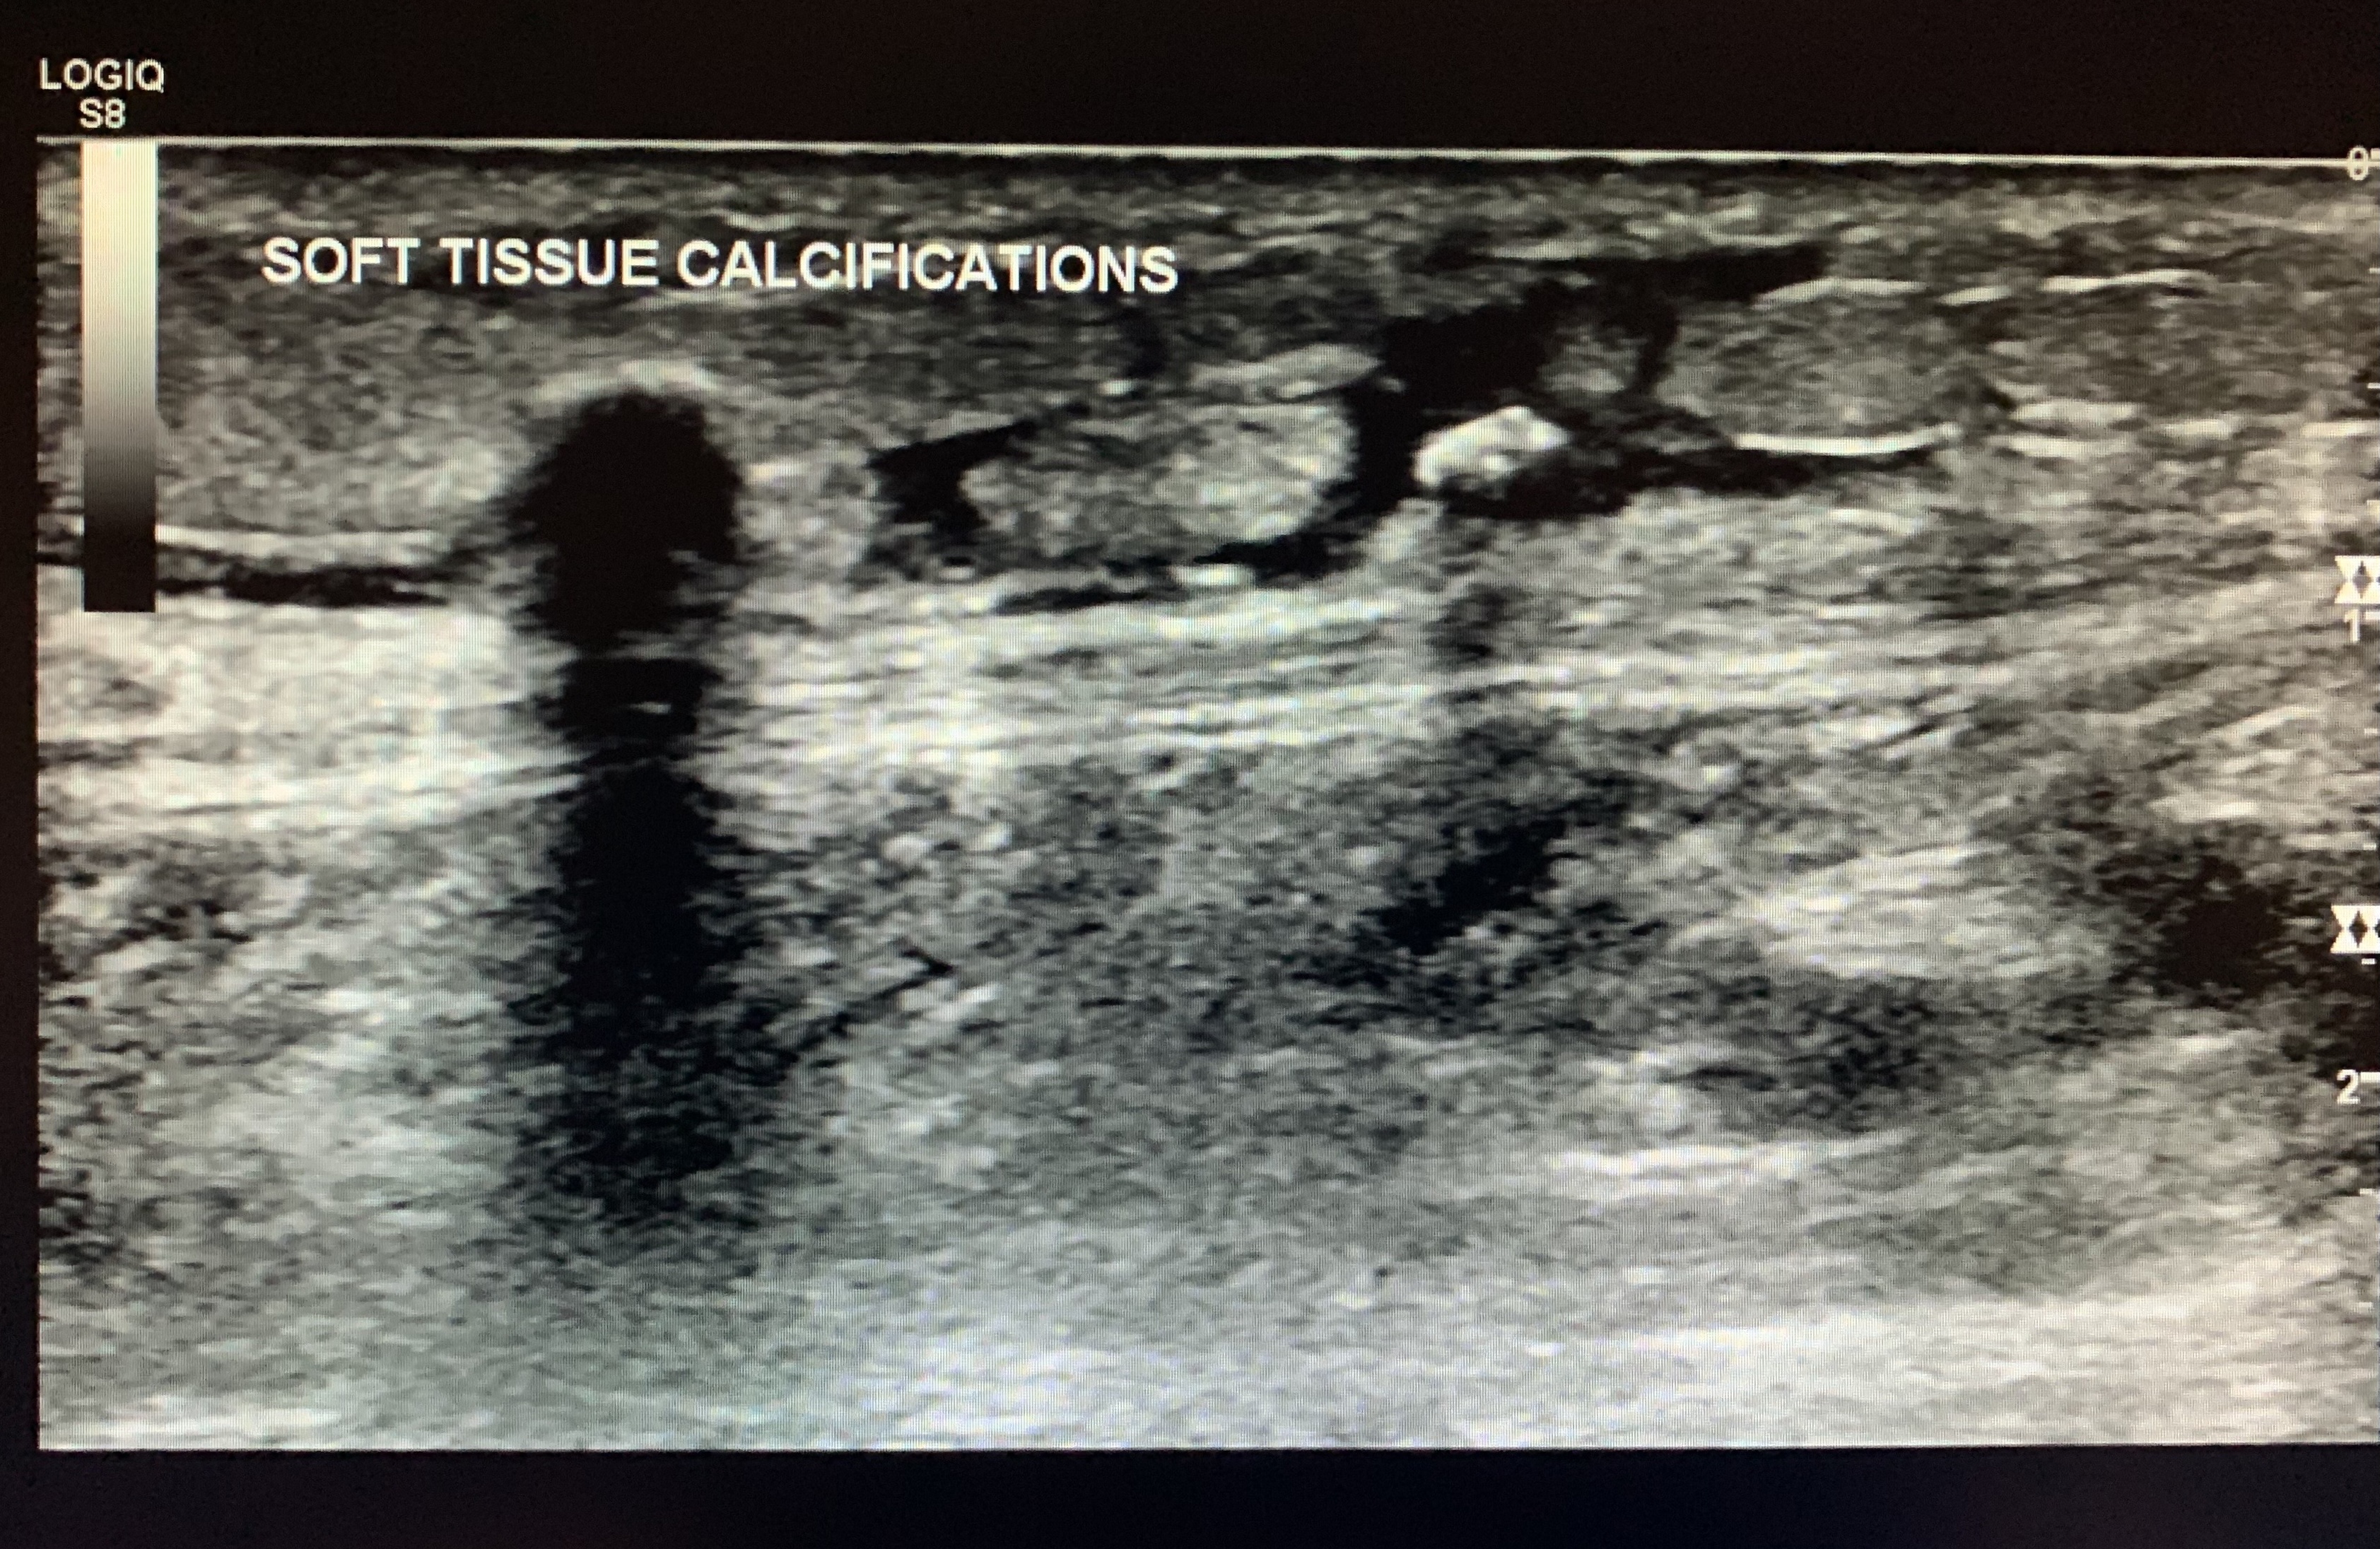

Asses for edema, calcifications, phleoboliths etc.